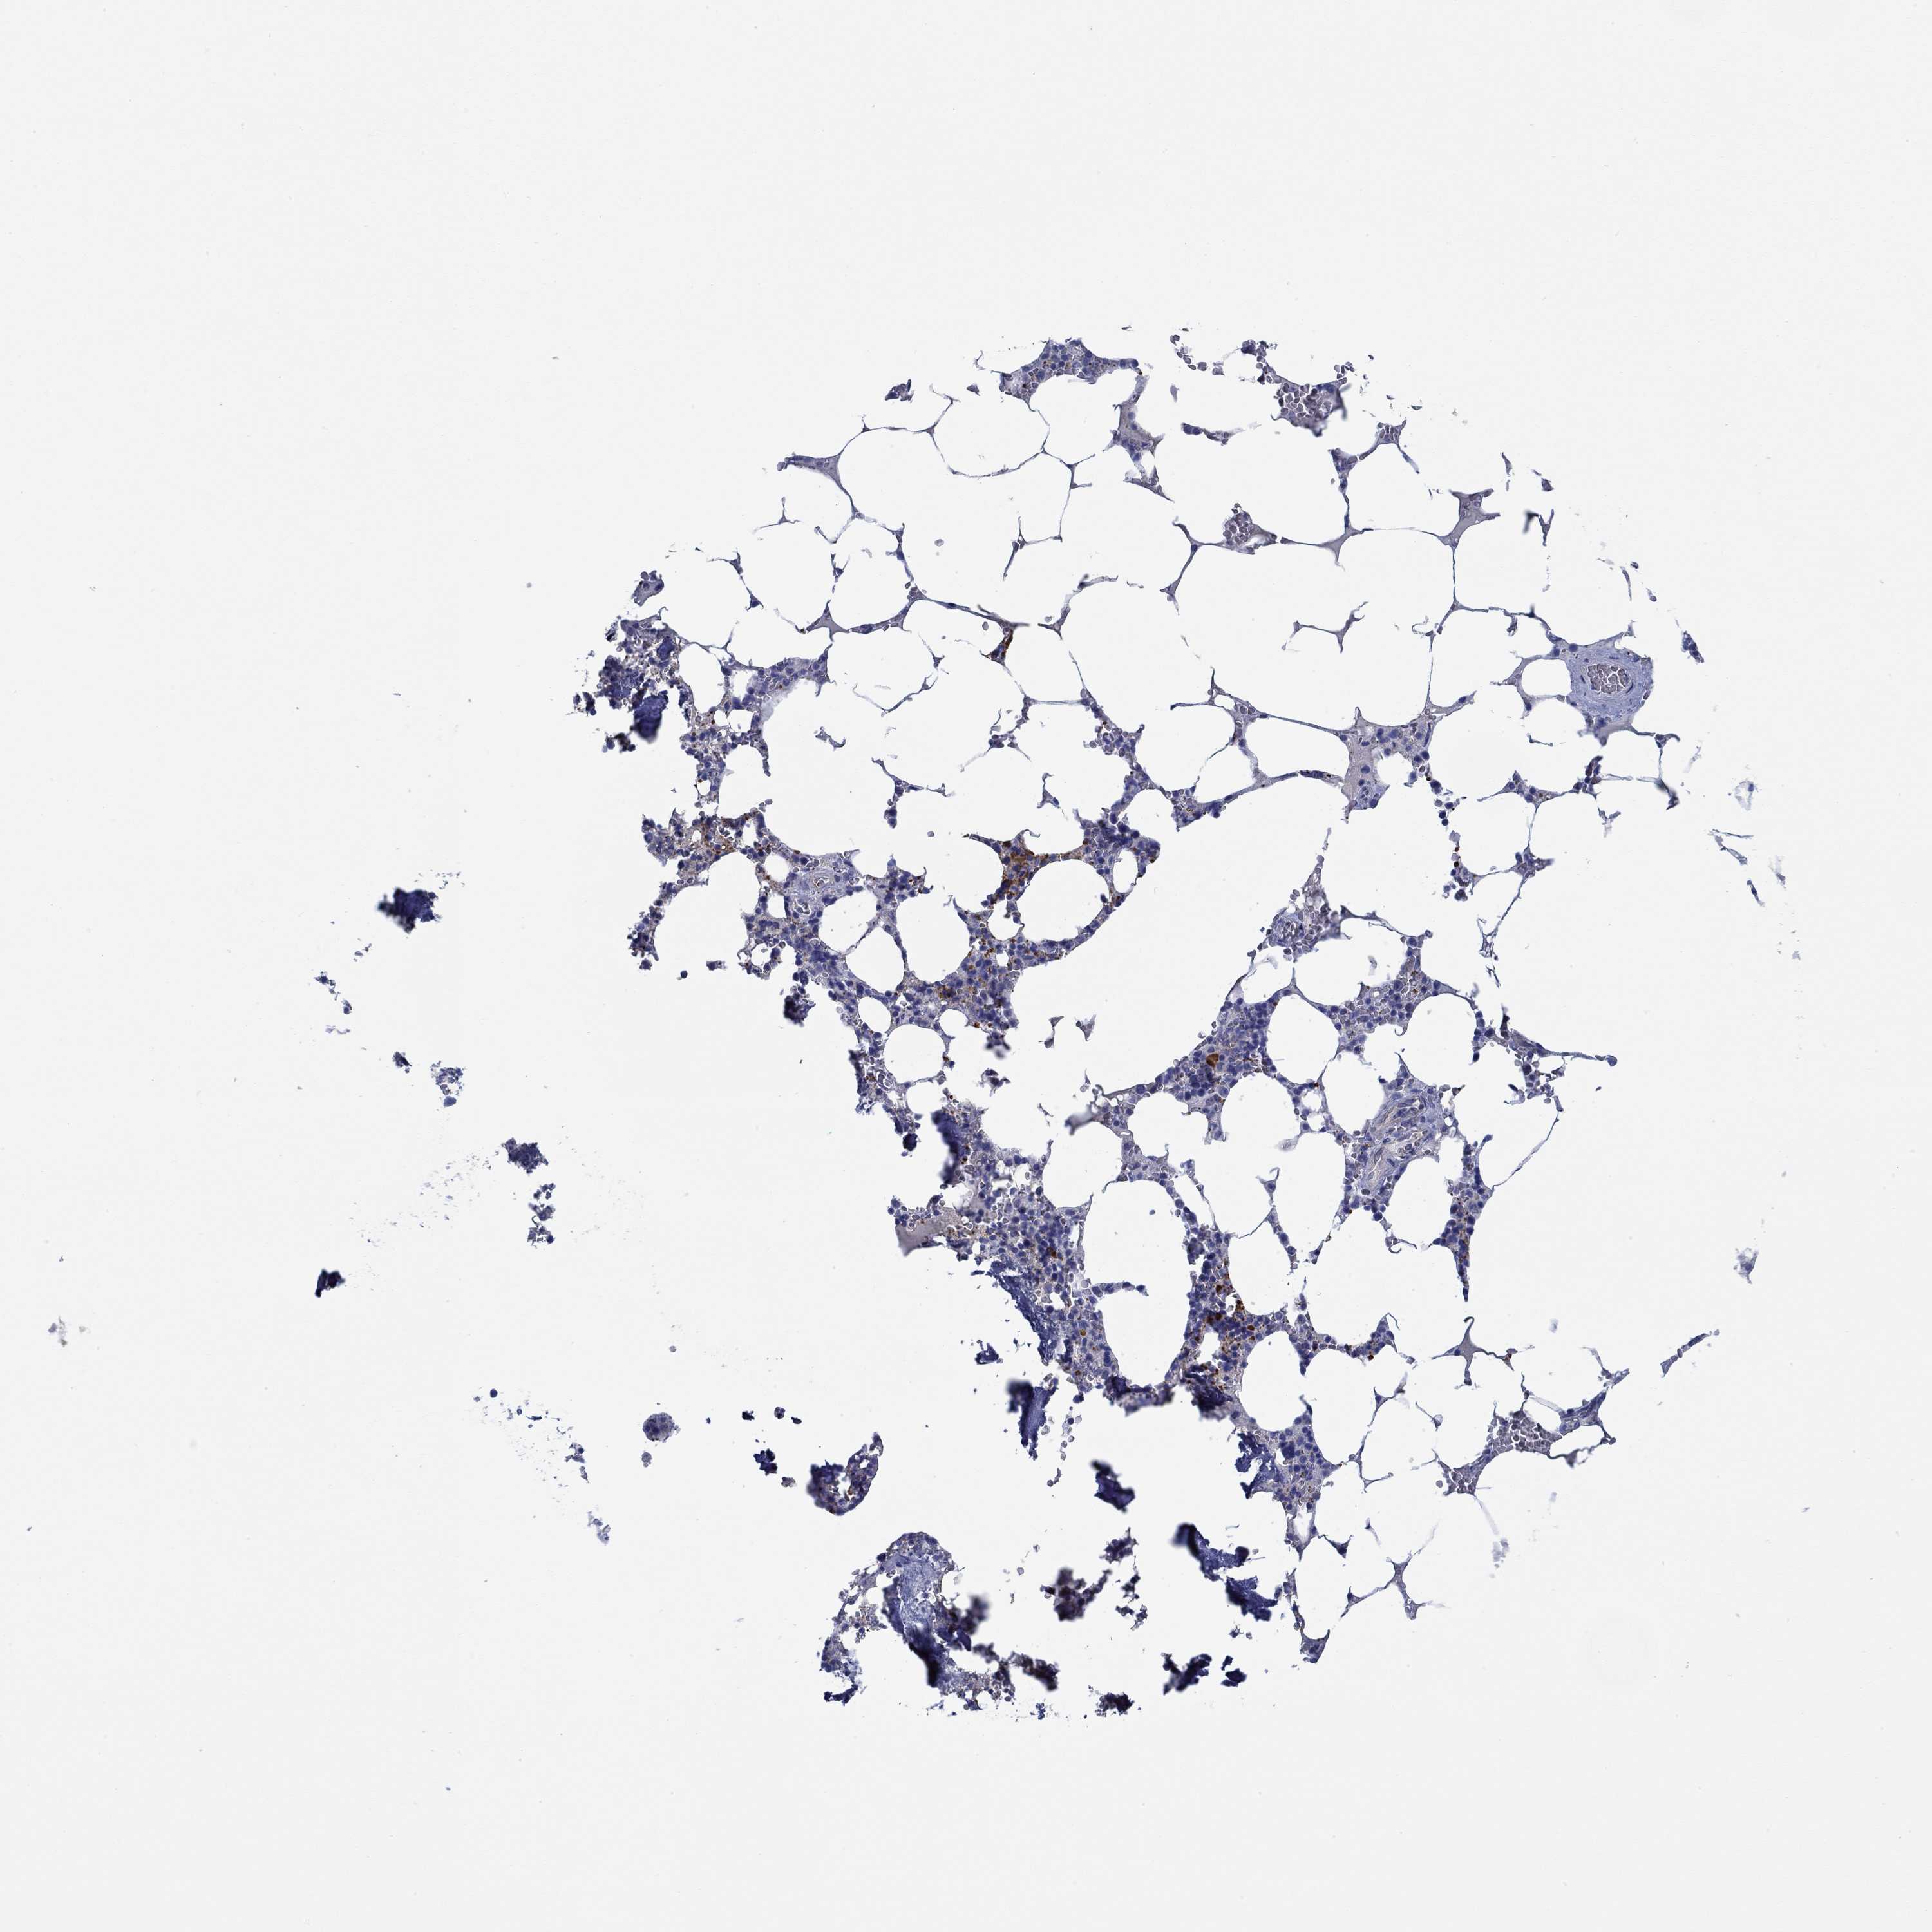

BONE MARROW - Antibody stainingi

Antibody staining in the annotated cell types in the current human tissue is reported as not detected, low, medium, or high, based on conventional immunohistochemistry profiling in selected tissues. This score is based on the combination of the staining intensity and fraction of stained cells.

Each image is clickable and will lead to virtual microscopy that enables deeper exploration of all samples and also displays staining intensity scores, fraction scores and subcellular localization as well as patient and tissue information for each sample.

Antibody HPA067508Antibody CAB080514Antibody CAB080517

Hematopoietic cells LowNot detectedLow